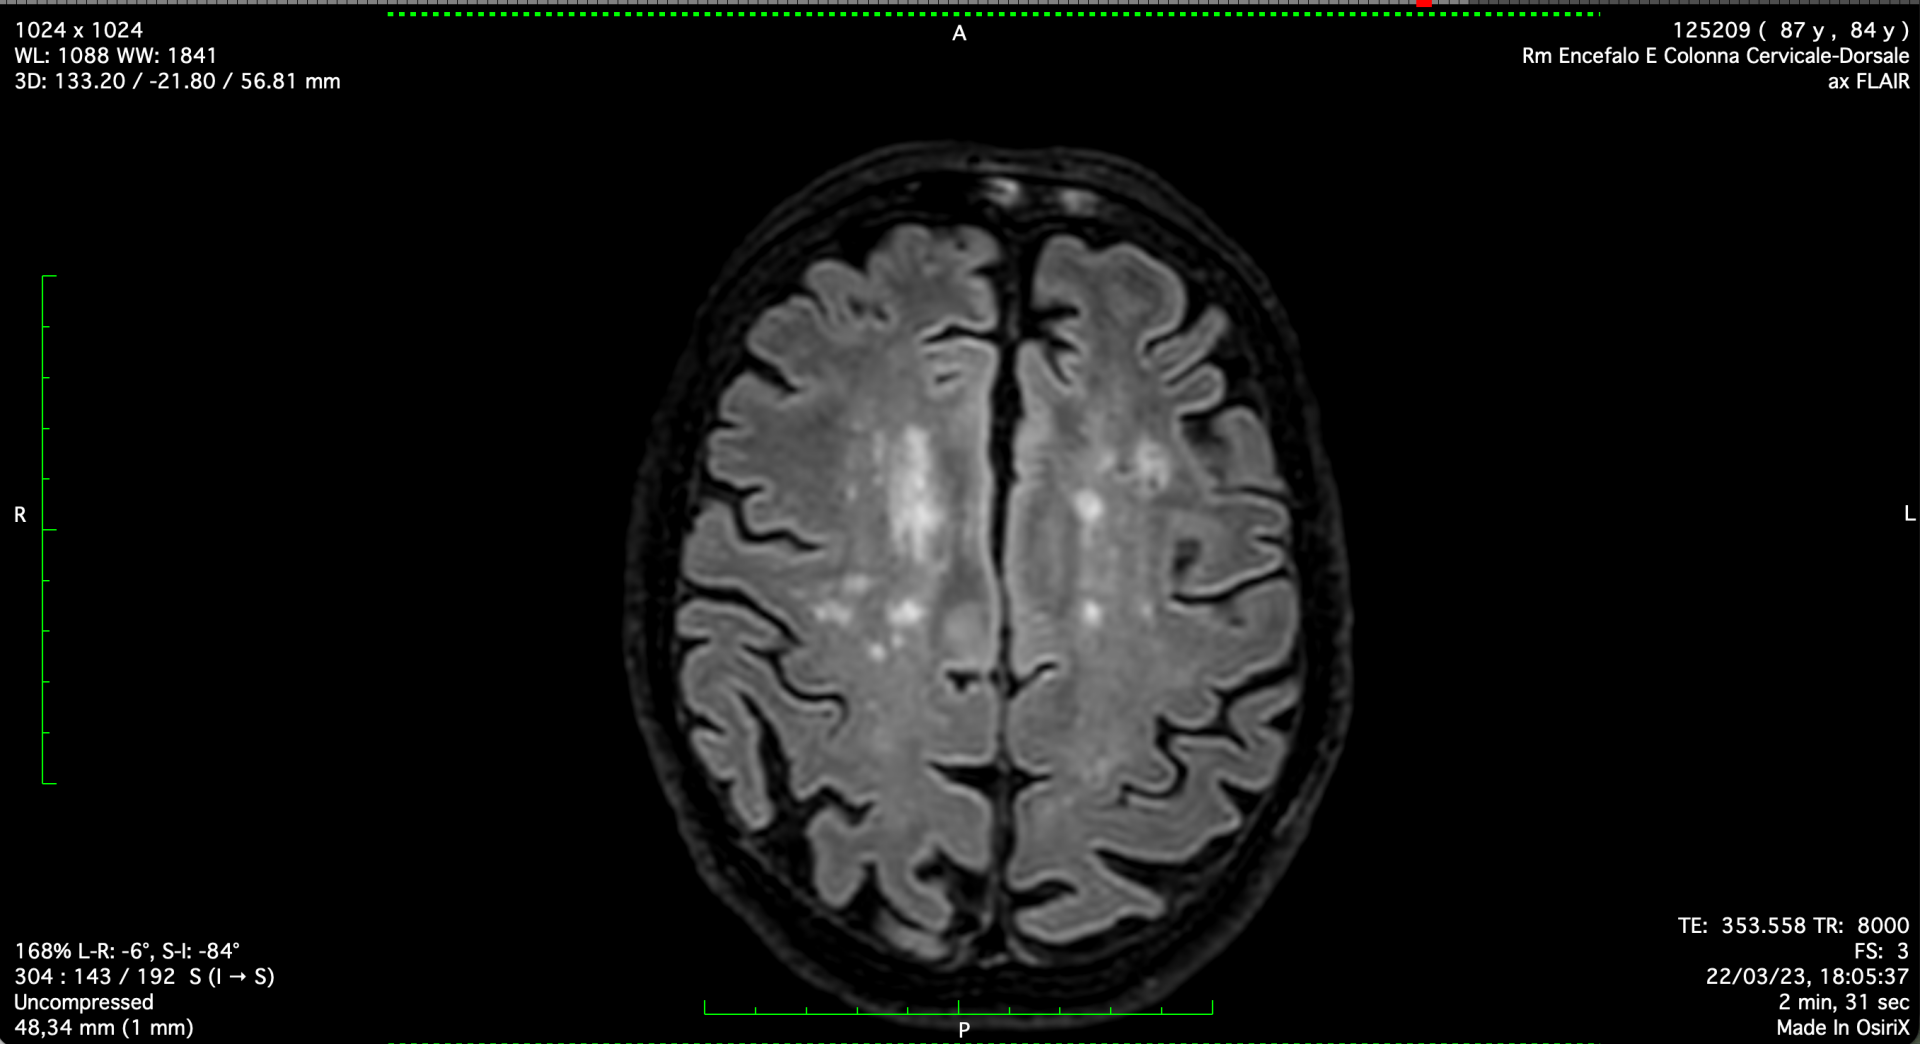

Since March 22nd, 2023, following the 3T MRI scan, a long journey with cysticercosis began, leading to a diagnosis and the correct initiation of albendazole treatment (400 mg b.i.d.). Either standard or increased doses, matching the maximum allowed (400 mg, two tablets t.i.d.), were prescribed, resulting in definitely positive clinical and imaging outcomes.

No farther than 19 months later, as of October 14th 2024, by directly tackling the responsible pathogen, the brain imaging (TC this time) appeared sufficiently normalised,  what's more corresponded by a perfect brain performance, completely regained from the previous assessment, when central neurological capability was affected (wake/sleep inversion, modified temper, paraparesis, and paraplegia),  and completely granting a normal, efficient, and functional relationship's life.